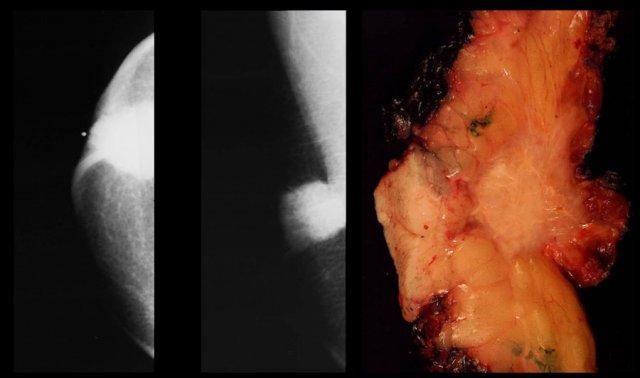

Hình bên trái cho thấy một khối lệch tâm, bờ không đều với các tua gai.

Nếu đây là bệnh nhân nữ, bạn sẽ không gặp khó khăn gì trong việc chẩn đoán đây là ung thư.

Ở nam giới cũng vậy.

Ung thư vú ở nam giới biểu hiện là một khối tròn, bầu dục hoặc bờ không đều.

Vôi hóa hiếm gặp, nhưng khi xuất hiện thì thường thô hơn so với ở nữ giới.

Hình bên trái là một ung thư biểu mô ống tuyến xâm nhập nhỏ.

Tổn thương nằm ở vùng dưới quầng vú và trung tâm, nhưng có vỏ bao.

Đây không phải là gynecomastia.

Bệnh Paget của núm vú và loét da gặp phổ biến hơn so với ở nữ giới.

Hình bên trái là ung thư biểu mô ống tuyến xâm nhập kèm co rút da.